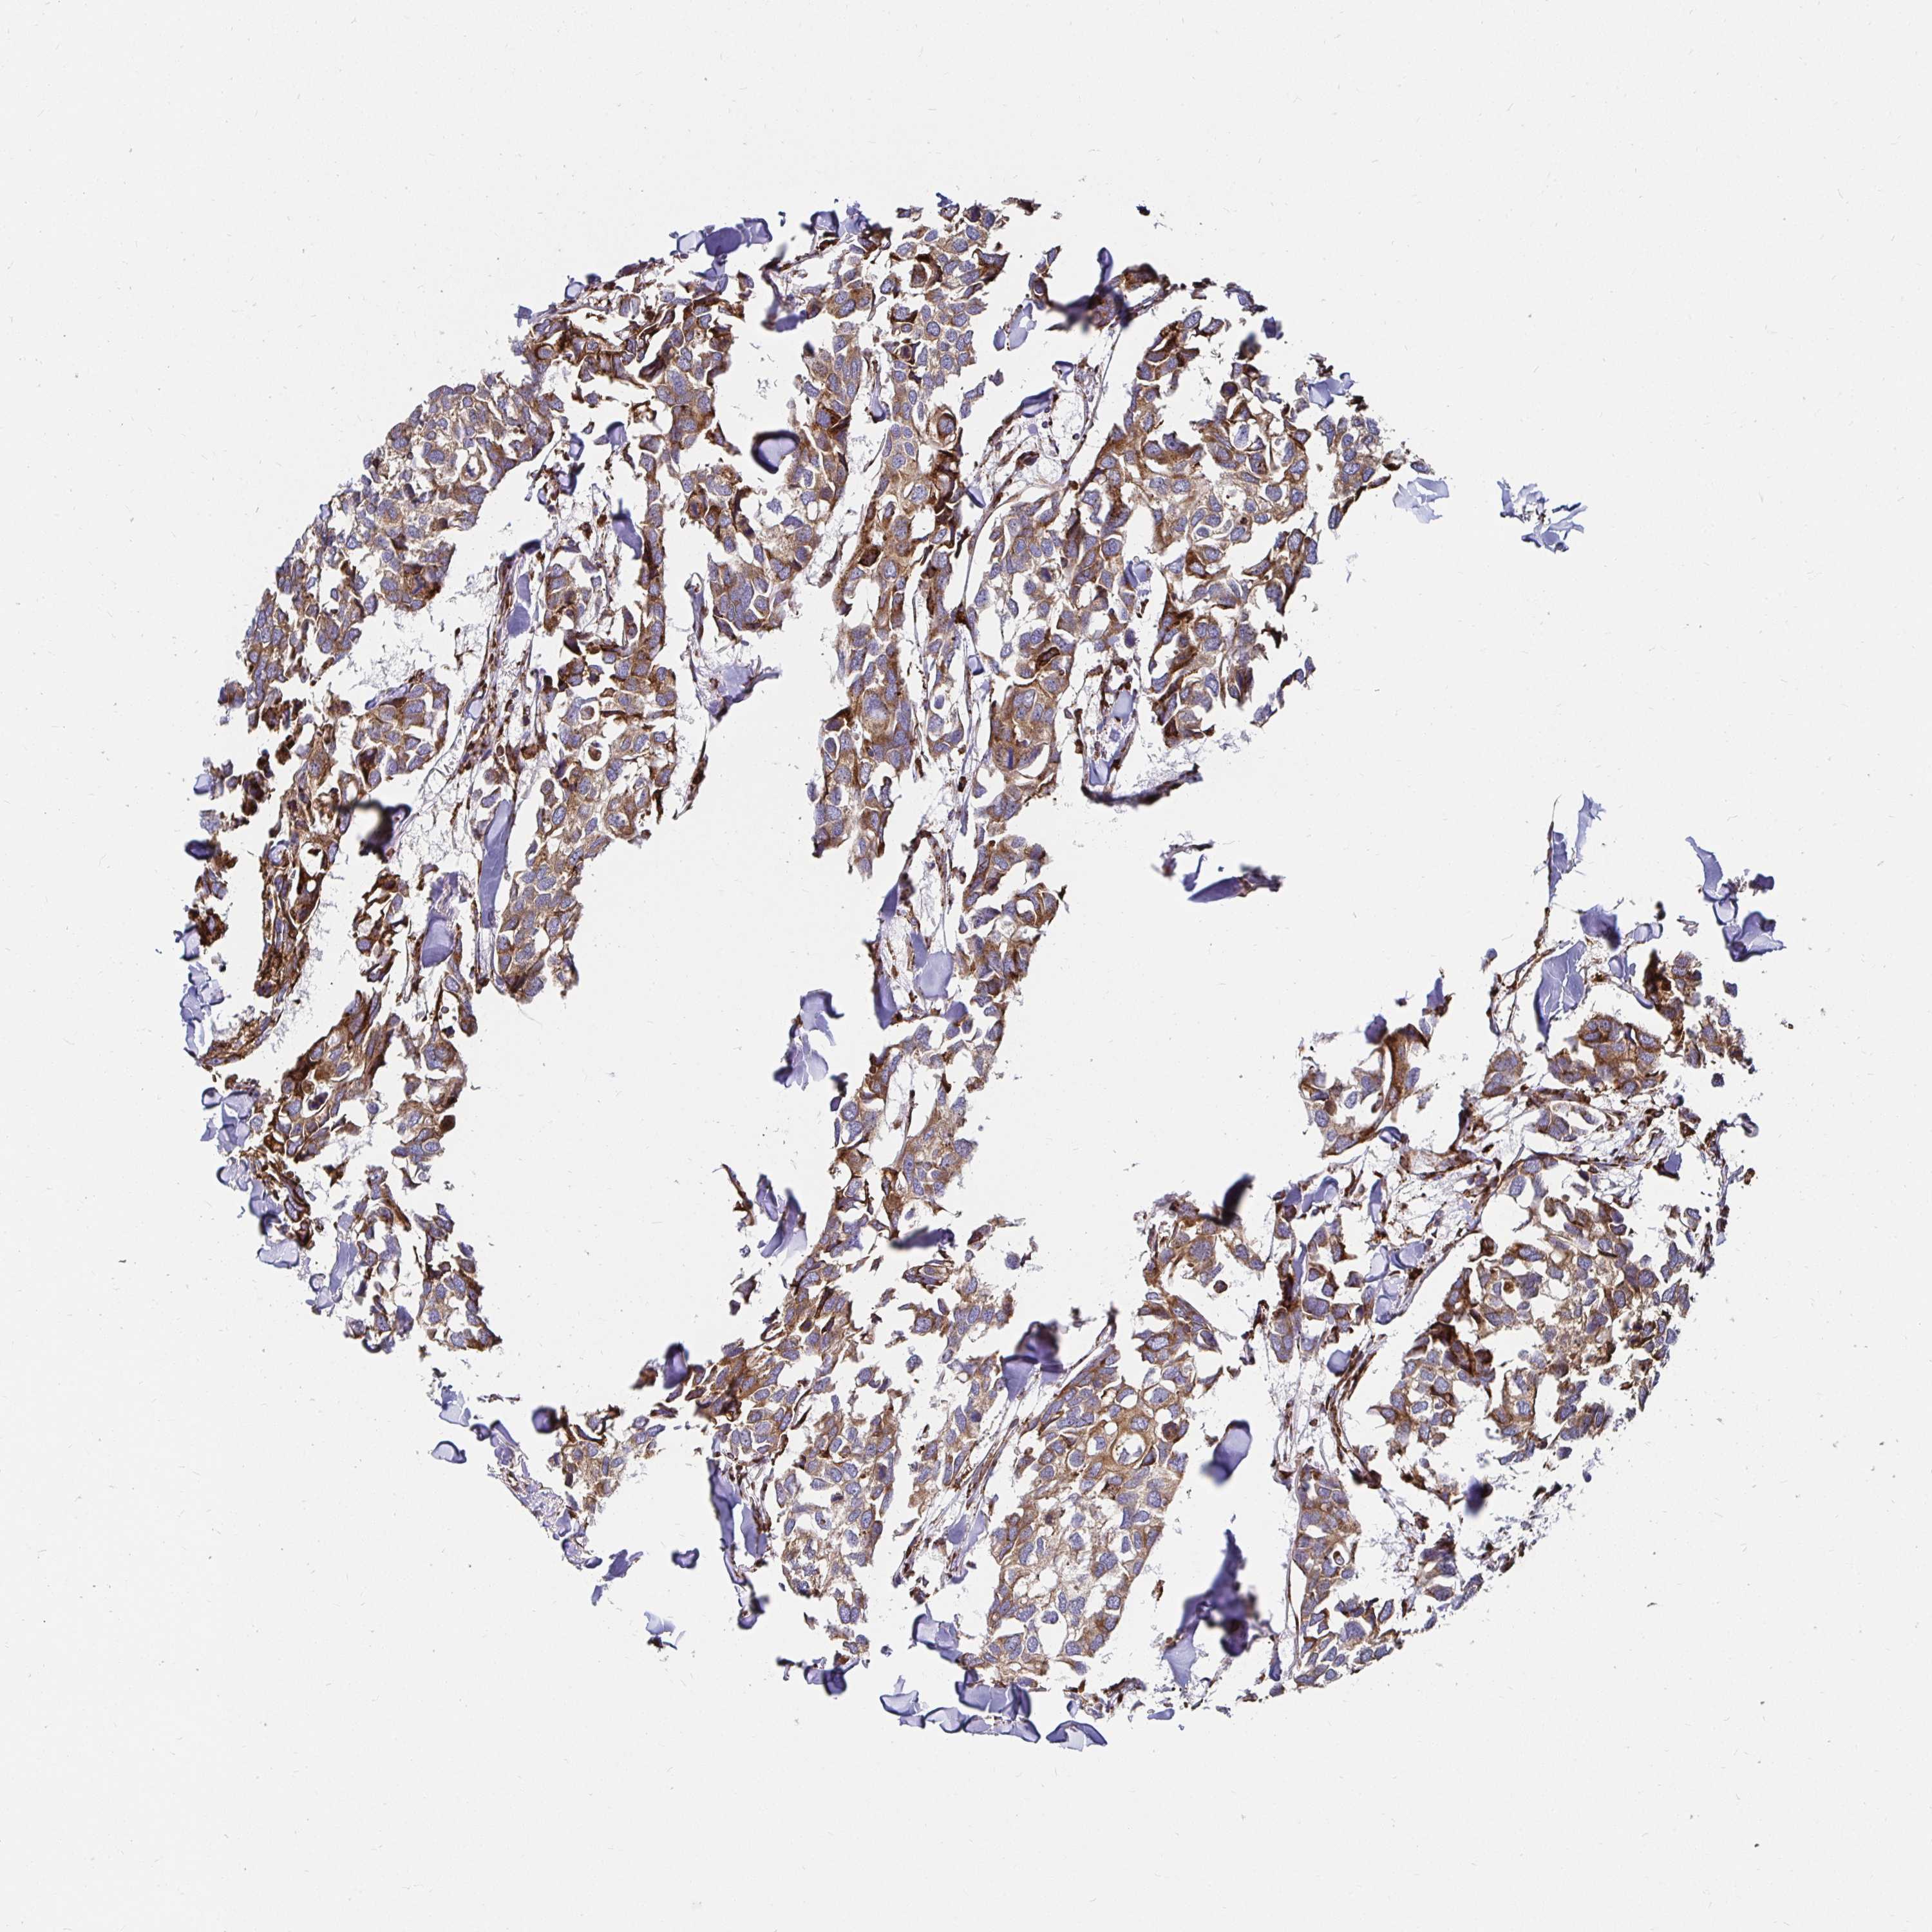

CANCER BREAST CANCER Show tissue menu

BRCA TCGA BRCA VALIDATION PROTEIN EXPRESSION